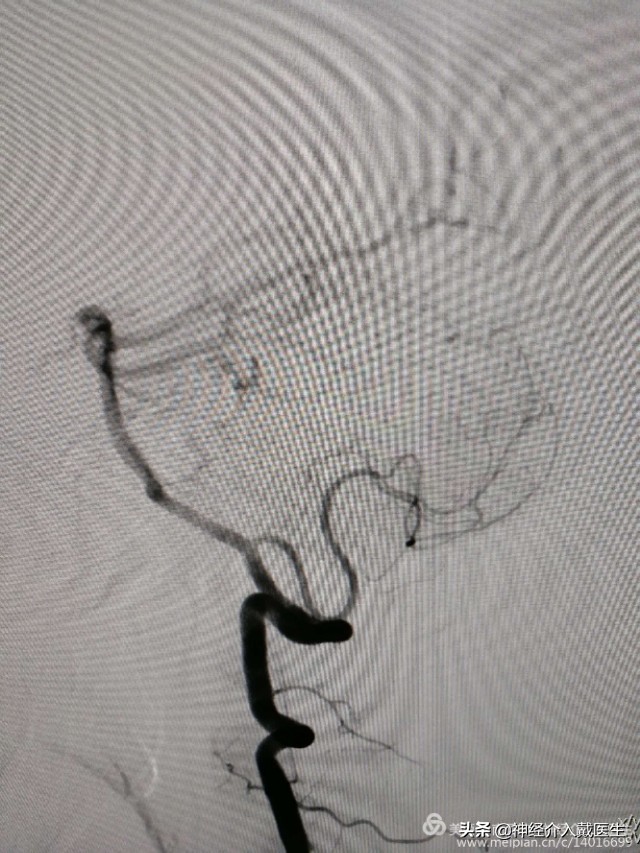

通过真腔放置支架导管,放置弹簧圈导管,释放一个5mm*12cm弹簧圈后,考虑需要保护小脑后下动脉,支架网孔大小很重要,我们选择Enterprise2支架,4mm*23mm一枚,

依次释放6mm*9cm,4mm*8cm,2mm*2cm,2mm*2cm弹簧圈各一枚,造影显示动脉瘤腔致密栓塞。

复查椎动脉正位,动脉瘤不显影,载瘤动脉及右侧小脑后下动脉通畅。

复查椎动脉侧位,动脉瘤不显影,载瘤动脉及右侧小脑后下动脉通畅。遂结束手术。